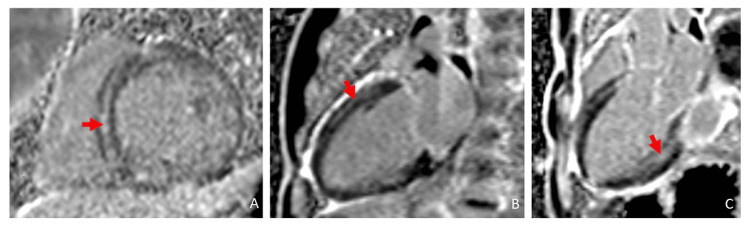

CMR demonstrated a mildly dilated left ventricle with global hypokinesis (LVEF 34%). There was markedly abnormal multifocal late gadolinium enhancement involving multiple myocardial layers (Figure 3).

The findings were most consistent with substance abuse associated with catecholaminergic myocardial injury (mid-wall late gadolinium enhancement (LGE)) and vasospastic infarction (subendocardial late gadolinium enhancement). There was expanded interstitial volume (ECV of 47%) quantified at the septal segment, which indicated replacement fibrosis (Figure 4). There was no evidence of acute edema/inflammation based on a normal T2 mapping. He was discharged on guideline-directed medical therapy and substance abuse counseling and rehabilitation. He subsequently was admitted to a halfway house for substance abuse rehabilitation.